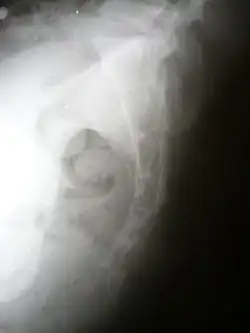

| Lateral radiograph showing a fracture of the coccyx, as well as a lower lumbar fracture | |